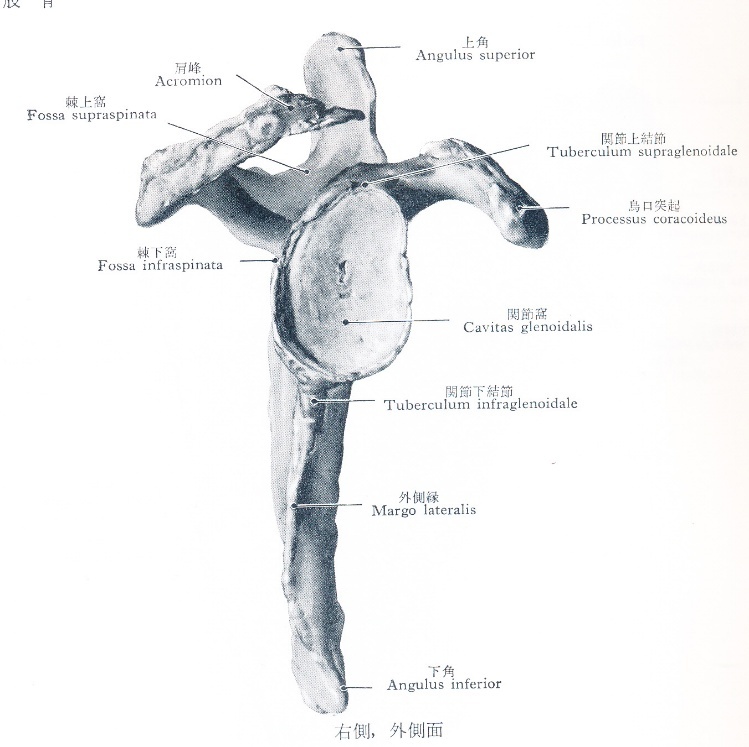

解剖学的には肩甲上腕関節は球関節に分類されますが、下肢は歩くことにほぼ特化されていますので関節は深い球関節になってがっちりと体重を支えています(図2)。上肢は色々な方向に動くため肩甲骨とは接している程度で浅い球関節になっています(図1、前々回 図2)。そのため肩関節のほうが脱臼しやすいのです。

出典:金子丑之助著「日本人体解剖学 第一巻」、南山堂、1956 図1.肩関節

上腕骨骨頭は肩甲骨の関節窩に接し、

上は肩峰がかぶさっている。